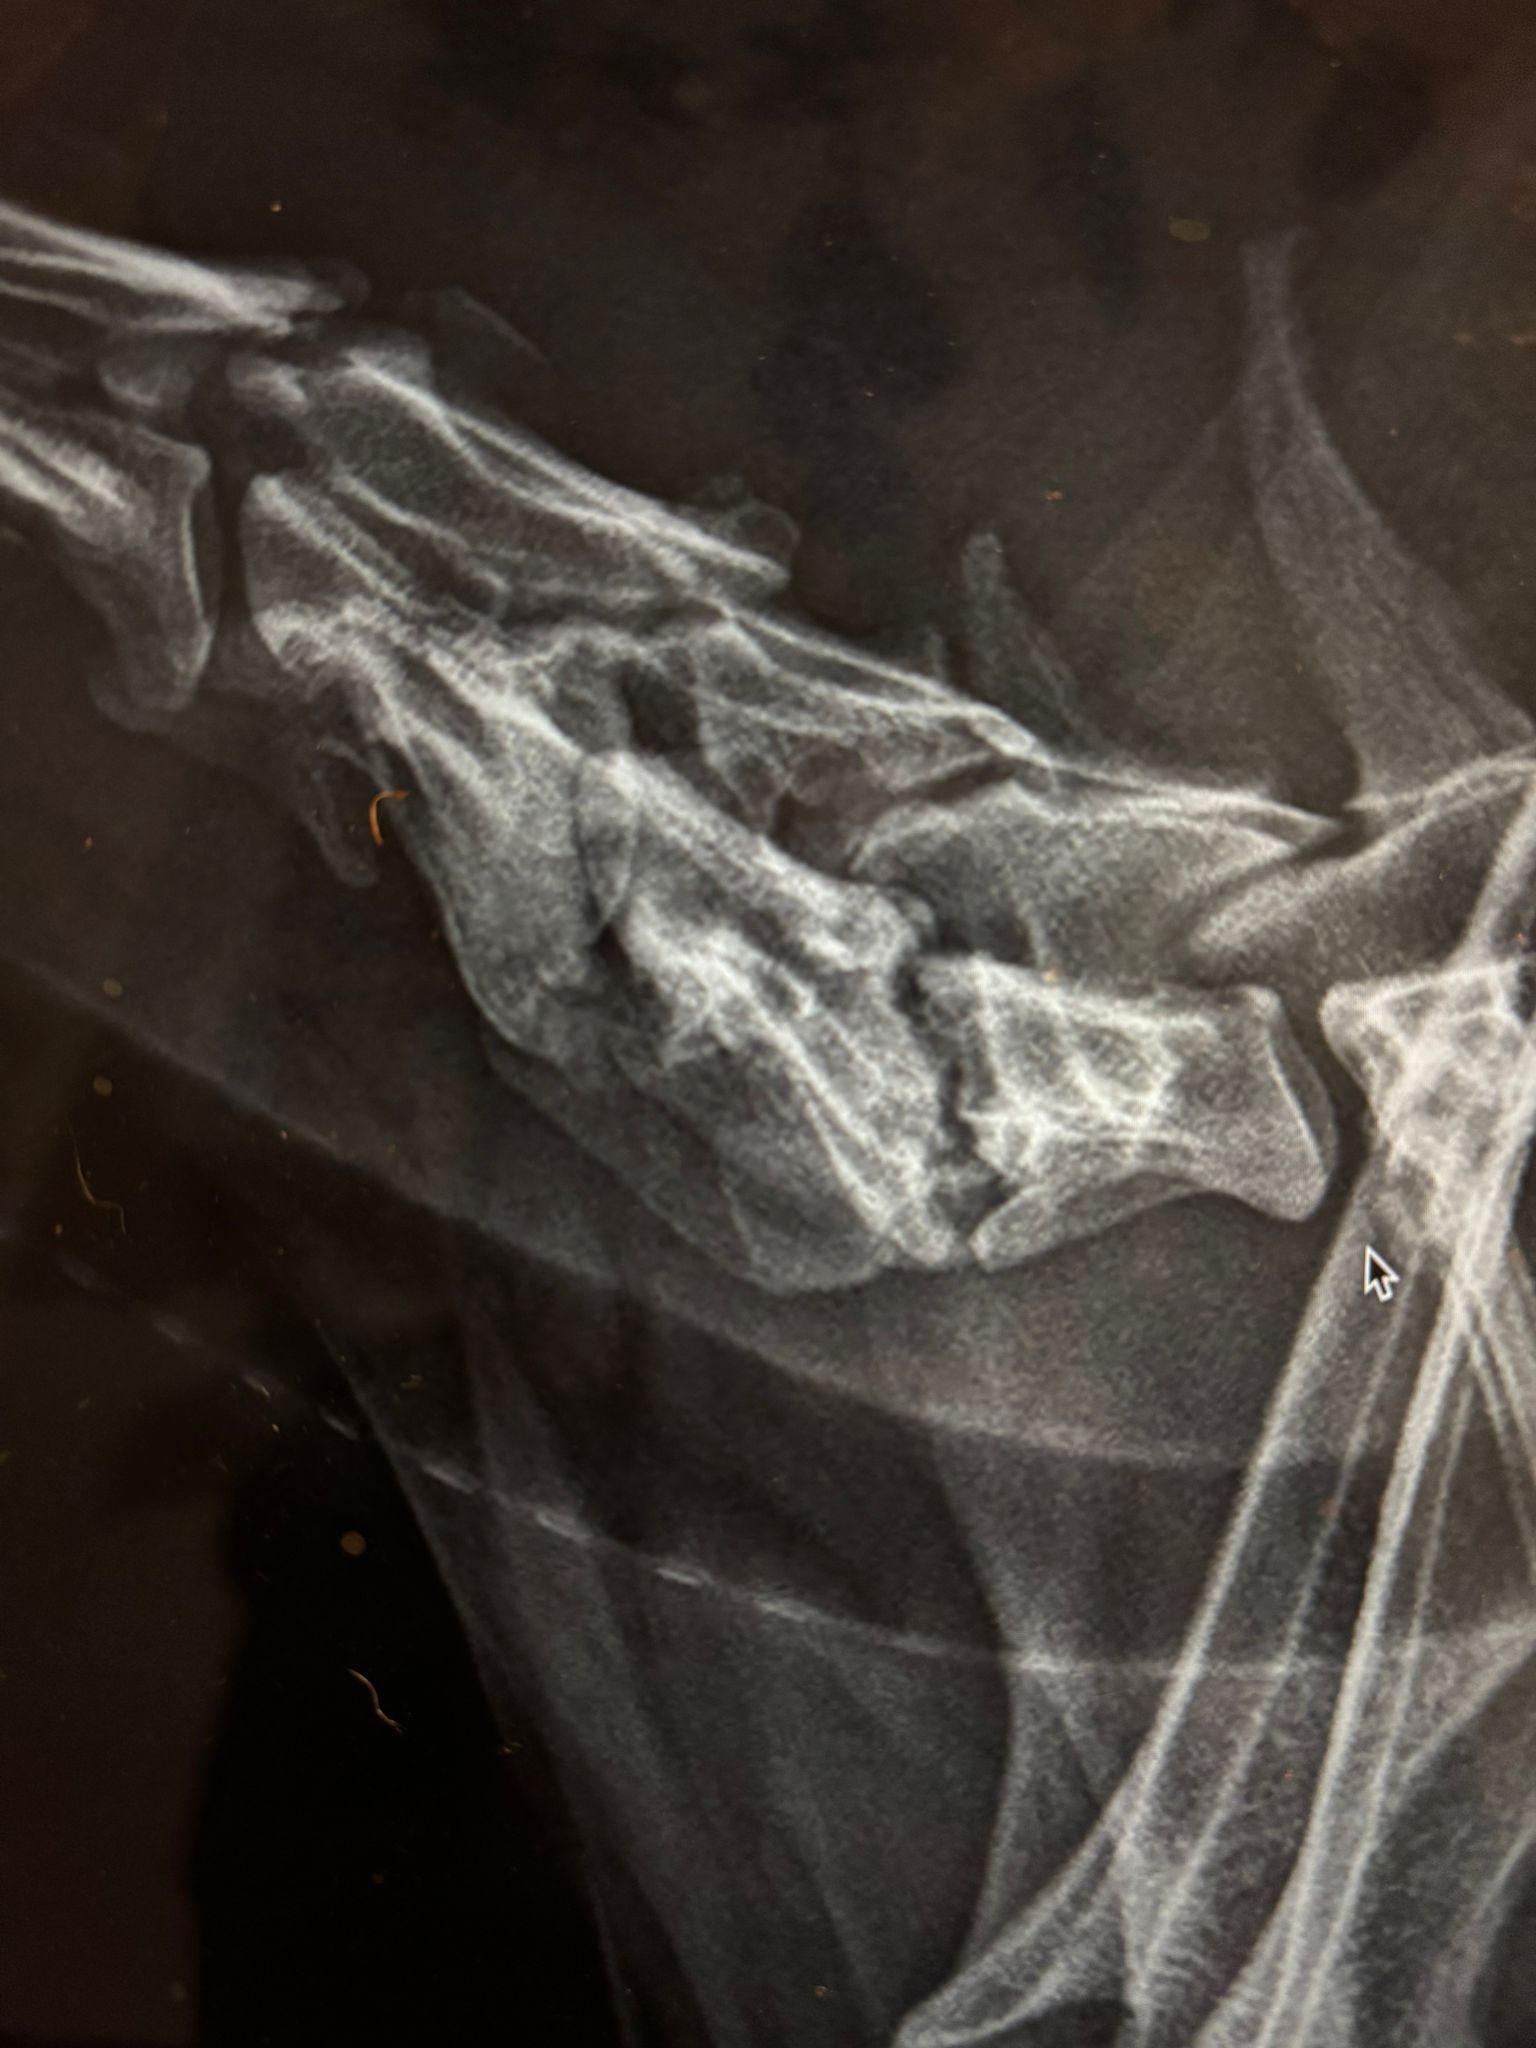

Beim Tierarzt wurden dann weitere Untersuchungen durchgeführt und u.a. mehrere Röntgenbilder gemacht.

Das Ergebnis war für alle überraschend. An 3 Halswirbeln zeigten sich ausgeprägte Veränderungen, die in den Gesichtern der Mediziner Fragezeichen hinterließen.

Um sich das genauer anzuschauen, war also weitere Diagnostik notwendig. Alma bekam Schmerzmittel und wir vereinbarten einen Termin in der Uniklink Gießen.

Die Diagnose lautet Diskospondylitis (nicht mehr akut) mit Bandscheibenveränderungen und Spondylosen.

U.a. Zerstörung der vertebralen Endplatten an mehreren Wirbeln, Verengungen der Zwischenwirbelspalten und in einem Bereich ist die Bandscheibe derart verändert, dass man am Rückenmark schon erste Anzeichen einer Komprimierung sieht.

Was schlussendlich die Diskospondylitis ausgelöst hat und wann, können wir nicht mehr eruieren. Sie ist zumindest nicht mehr aktiv und daher auch nicht behandlungsbedürftig. Die Veränderungen an den Wirbeln und Bandscheiben sind aber nun leider da und auch nicht reversibel. Auch erste Arthrosen lassen sich bereits erkennen.